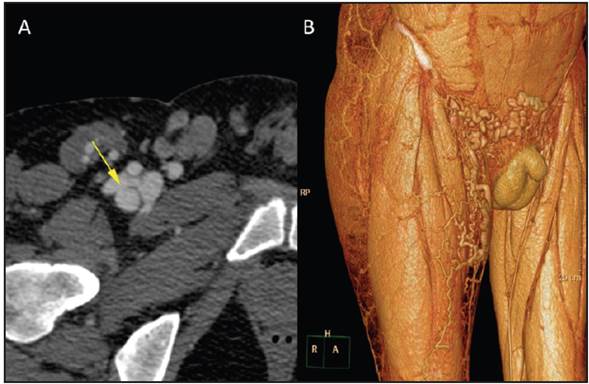

Figure 2 (A): an axial view of an iliofemoral computed tomography angiography of the connection between the anterior wall of the deep femoral artery and a blind venous sac connecting to the femoral vein. Note the mix of contrast in the venous territory in an arterial phase; (B): volumetric reconstruction of the iliofemoral computed tomography angiography in the venous phase, showing pre-pubic and right proximal thigh varicose bundles stemming from venous insufficiency driven by deep vein thrombosis.

Figure 3 Volumetric reconstruction of the iliofemoral computed tomography angiography (A): frontal plane; (B): sagittal plane. The arrow indicates the ante rior wall of the proximal third of the deep femoral artery, as well as a blind venous sac draining to the femoral vein, with aneurysmal dilation of the iliac vein.